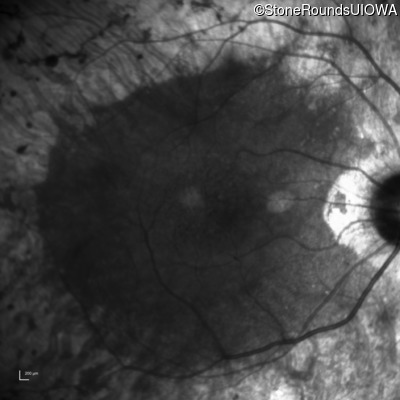

Age at visit: 46 years

This 46 year old man has had poor vision in dim light since age 2.

Diagnosis & molecular findings

AR Retinitis Pigmentosa SLC24A1 Met252 del2ggaAT Leu1052 del2ctTC AR